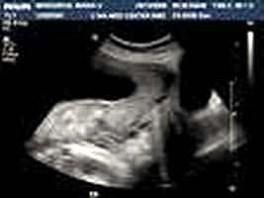

问题 图中的胎盘为?(?)

选项 A.完全性前置胎盘 B.部分性前置胎盘 C.边缘性前置胎盘 D.低置胎盘 E.以上都不是

答案 A